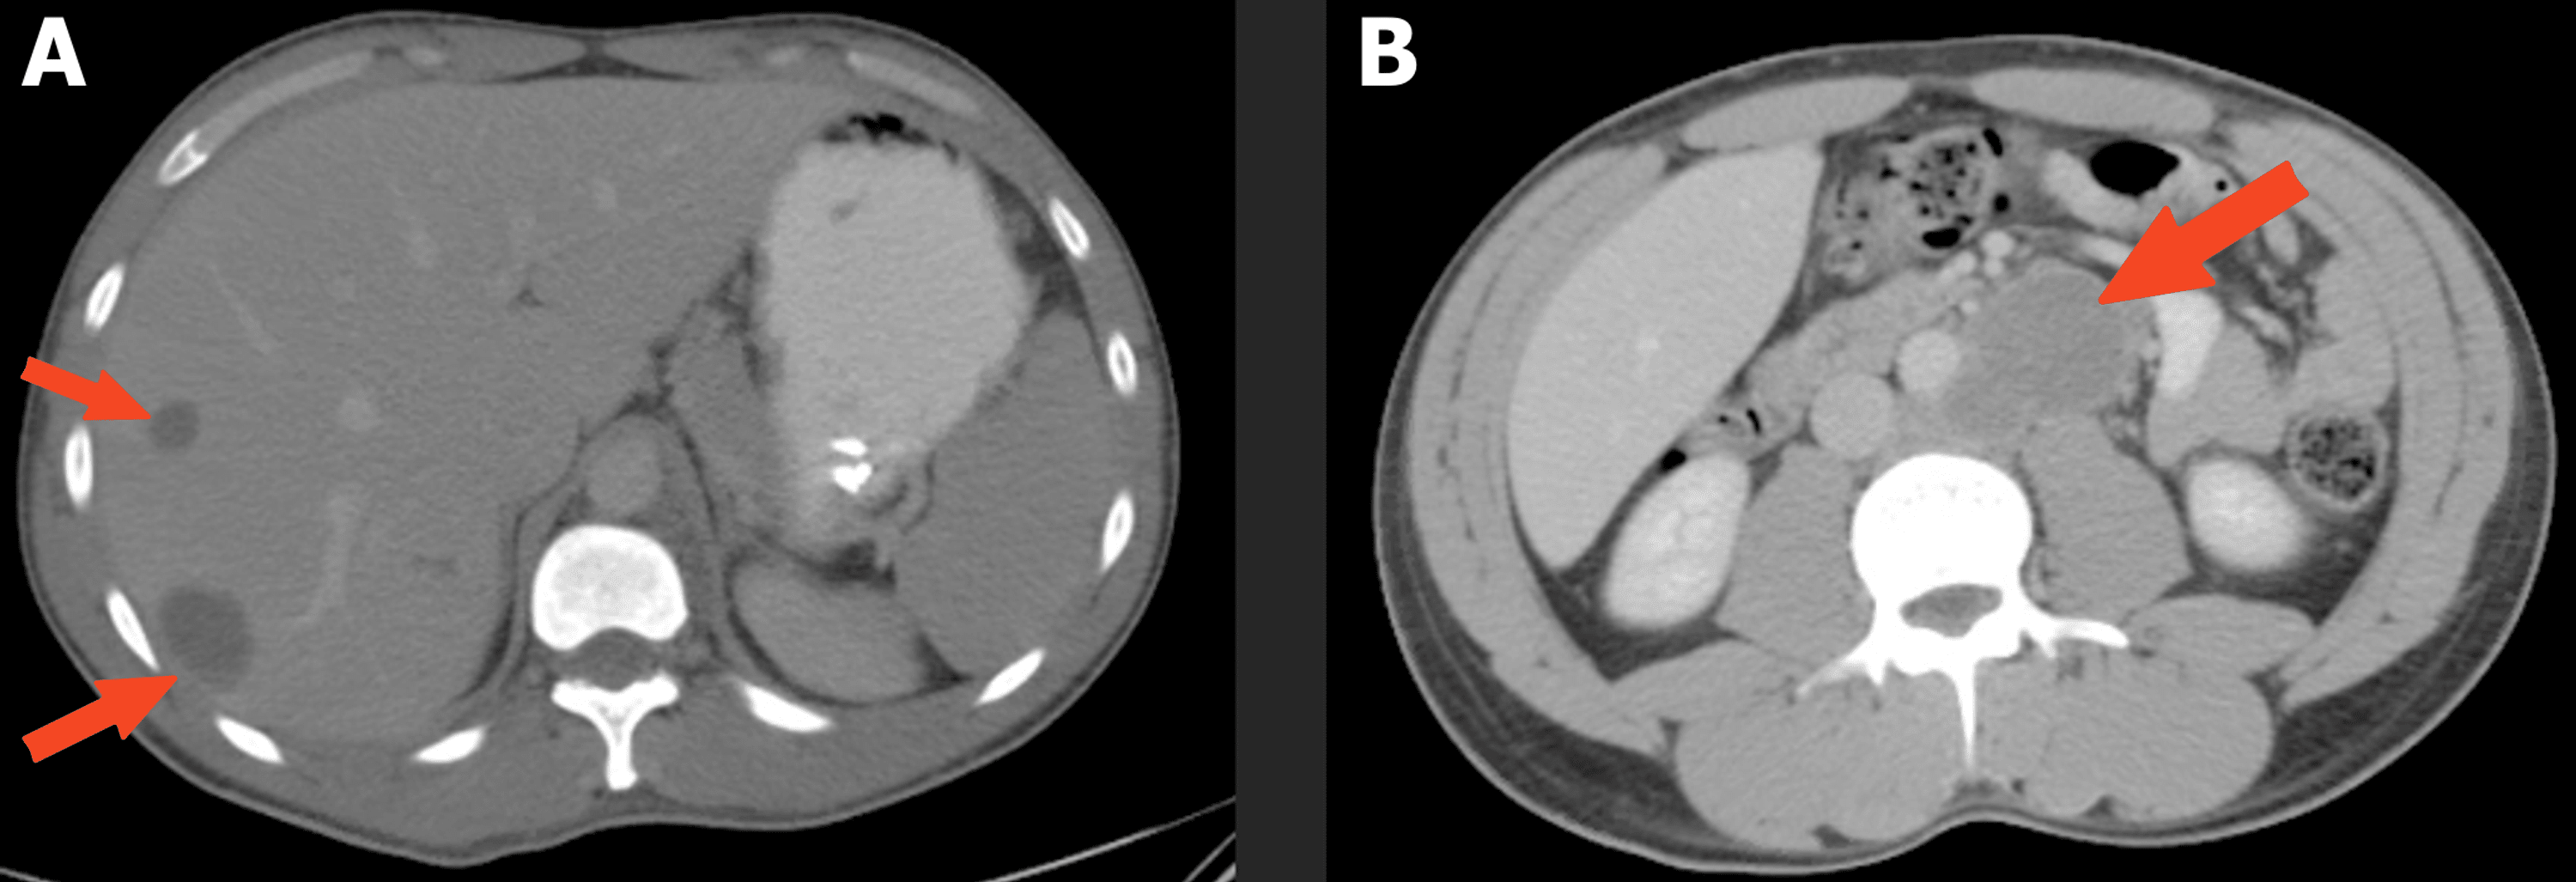

Brain CT of a young man with testicular germ cell tumor is showing

(PDF) Imaging features of brain metastases from testicular cancer Testicular Cancer Brain Metastases Symptoms Signs and symptoms caused by brain metastases can vary based on the location, size and rate of growth of the metastatic. A feeling of heaviness in. 1 most cases with brain. common treatments for brain metastases from testicular primary cancers include surgical resection, whole brain. testicular cancer with neurological symptoms indicates brain metastases. A lump or swelling in. Testicular Cancer Brain Metastases Symptoms.